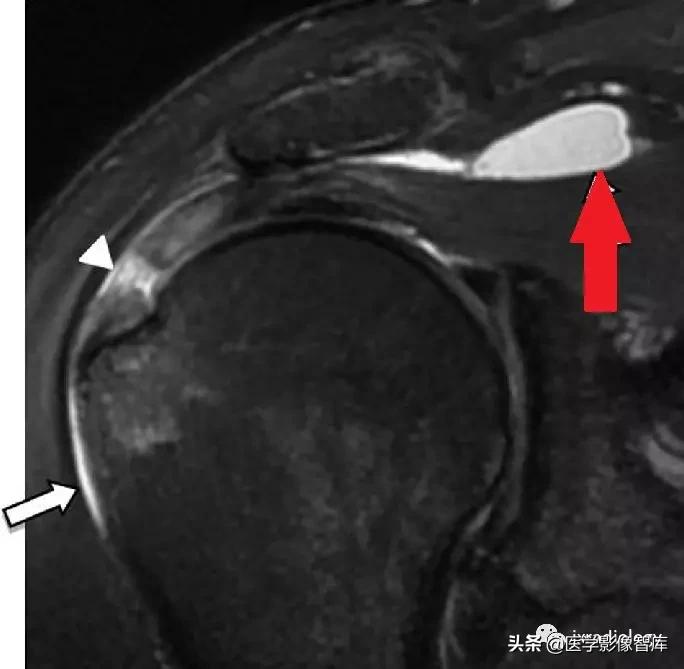

图4:肩峰下 - 三角肌下滑囊内侧延伸

红箭:肩峰下 - 三角肌下滑囊内侧延伸

箭头:冈上肌肌腱撕裂

白箭:肩峰下 - 三角肌下滑囊